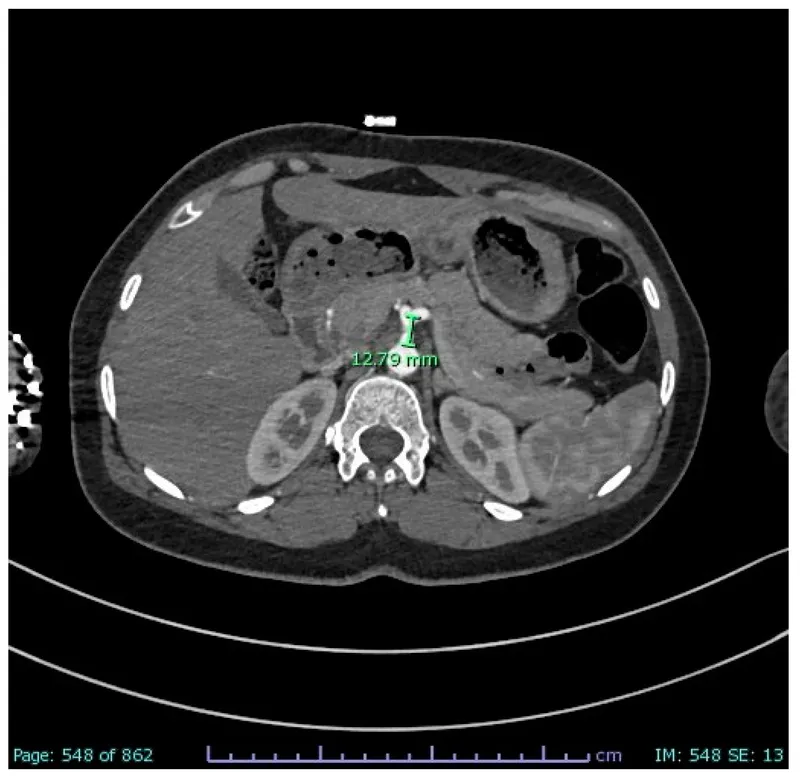

Axial Slice @ L2/L3 - The Nutcracker Crunch

- Key Structures: Kidneys, renal vessels, aorta, IVC, superior mesenteric artery (SMA), and duodenum.

- Vascular Relationship: The left renal vein (LRV) courses between the SMA anteriorly and the abdominal aorta posteriorly.

- Clinical Correlation: Compression of the LRV in this "nutcracker" can lead to renal venous hypertension, causing hematuria and flank pain.

⭐ Exam Favourite: Nutcracker syndrome is a key cause of unexplained left-sided varicocele, as the left gonadal vein drains into the high-pressure LRV.

- The left renal vein's path between the aorta (posteriorly) and SMA (anteriorly) is a classic anatomical relationship (Nutcracker syndrome).